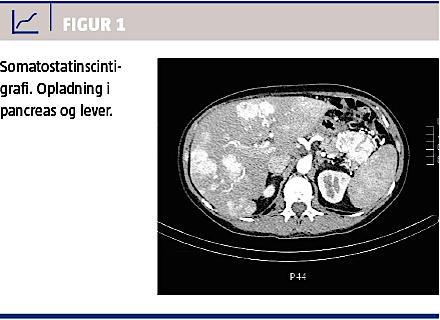

Patienten blev diagnosticeret med en neuroendokrin tumor i pancreas med et Ki-67-proliferationsindeks på 10% og metastasering til leveren (se Figur 1). En knoglescintigrafi udelukkede ossøse metastaser.